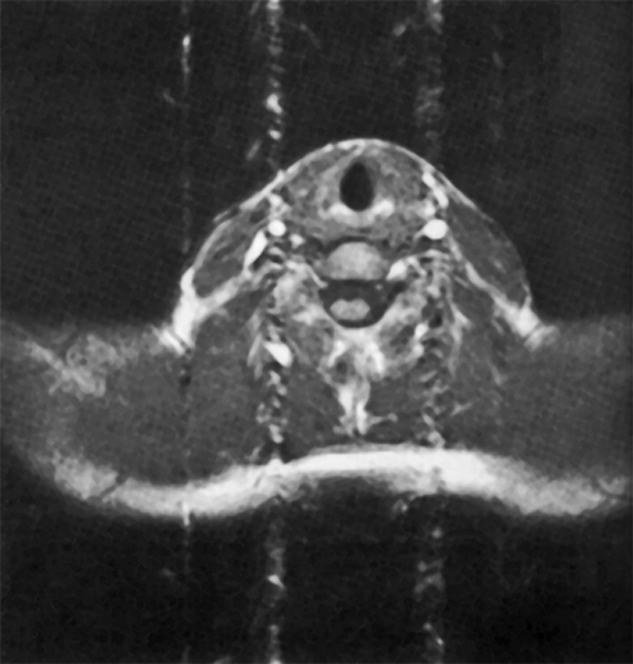

Figure 17-09:

Gradient-echo image of a neck with the pha­se en­coding gradient oriented ver­ti­cal­ly. Flow artifacts are ob­serv­ed as a column associated with arterial ves­sels